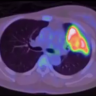

This video demonstrates the performance of a VATS trisegmentectomy on a patient with a left upper lobe cT1aN0 adenocarcinoma.